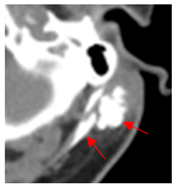

| 4 | 0–25 | 1923 | ![]() Axial CT image shows a mostly necrotic tumor in the left neck. | ![]() Axial CT image obtained 1 day after injection shows the NBTXR3 nanoparticles (arrows) in the tumor. |